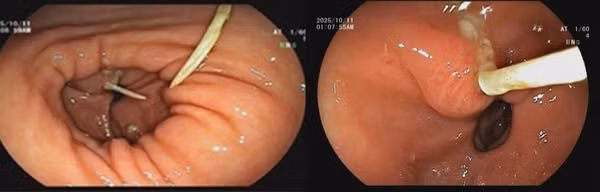

Kết quả nội soi dạ dày cho thấy: Sát môn vị có hình ảnh mảnh xương dài khoảng 3cm cắm vào thành dạ dày, vùng xung quanh phù nề, xung huyết nhiều và có loét. Khai thác tiền sử bệnh nhân cho biết, cách ngày vào viện 4 ngày bệnh nhân có ăn cháo gà, sau đó chỉ đau bụng âm ỉ nên chủ quan không đi khám.

Với sự phối hợp của các chuyên khoa, Bệnh nhân được tiến hành gây mê, nội soi can thiệp gắp dị vật, làm sạch vùng tổn thương và xử trí ổ loét.

manh-xuong-ga.jpg

Mảnh xương đâm xuyên dạ dày tạo ổ áp xe